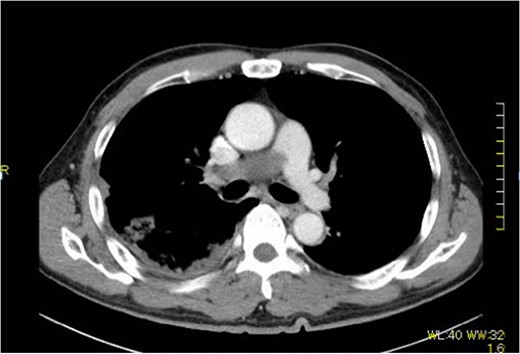

A 60-year-old man presenting with acute onset dyspnea and chest pain was referred to our institution. He had no past medical history. Physical examination was essentially normal except for weak respiratory sounds on the right side. Oxygen saturation was 88%. D-dimer was 1.43 mg/l. The electrocardiogram showed no ST changes. Chest radiography showed an abnormal shadow in the hilum of the right lung. Color Doppler ultrasound showed no deep vein thrombosis. Both the Wells Score and the Revised Geneva Score were 0. Transthoracic echocardiography showed normal left ventricular function (ejection fraction 62%), and no findings of pulmonary hypertension. Contrast-enhanced computed tomography (CT) showed a contrast defect lesion in the right and main pulmonary arteries, as well as a right pleural effusion (Fig. 1). He was initially diagnosed with PE according to the imaging findings and clinical presentation. Anticoagulant therapy (intravenous heparin infusion) was then started. Follow-up CT showed a larger defect lesion in the pulmonary artery, and the decision was then made to proceed with urgent pulmonary embolectomy because it was refractory to anticoagulant therapy. Cardiopulmonary bypass was established with aortic and bicaval cannulation. Deep hypothermic circulatory arrest was used every 10 minutes to obtain a bloodless field during pulmonary embolectomy. The right pulmonary artery was incised, and it was filled with a red, solid mass (Fig. 2). The mass was resected, and the pathological diagnosis during surgery was PAS. Because of the urgent situation, only endarterectomy, not pneumonectomy for radical resection of the tumor, was performed. On postoperative Day 7, CT showed residual lesions in the right pulmonary artery. The pathology report showed high-grade undifferentiated PAS (Fig. 3). The patient refused radical tumor resection by pneumonectomy, as well as postoperative radiation and chemotherapy. He died 5 months after the surgery.

Extensive contrast-deficient images ae present from the pulmonary artery trunk to the right pulmonary artery.